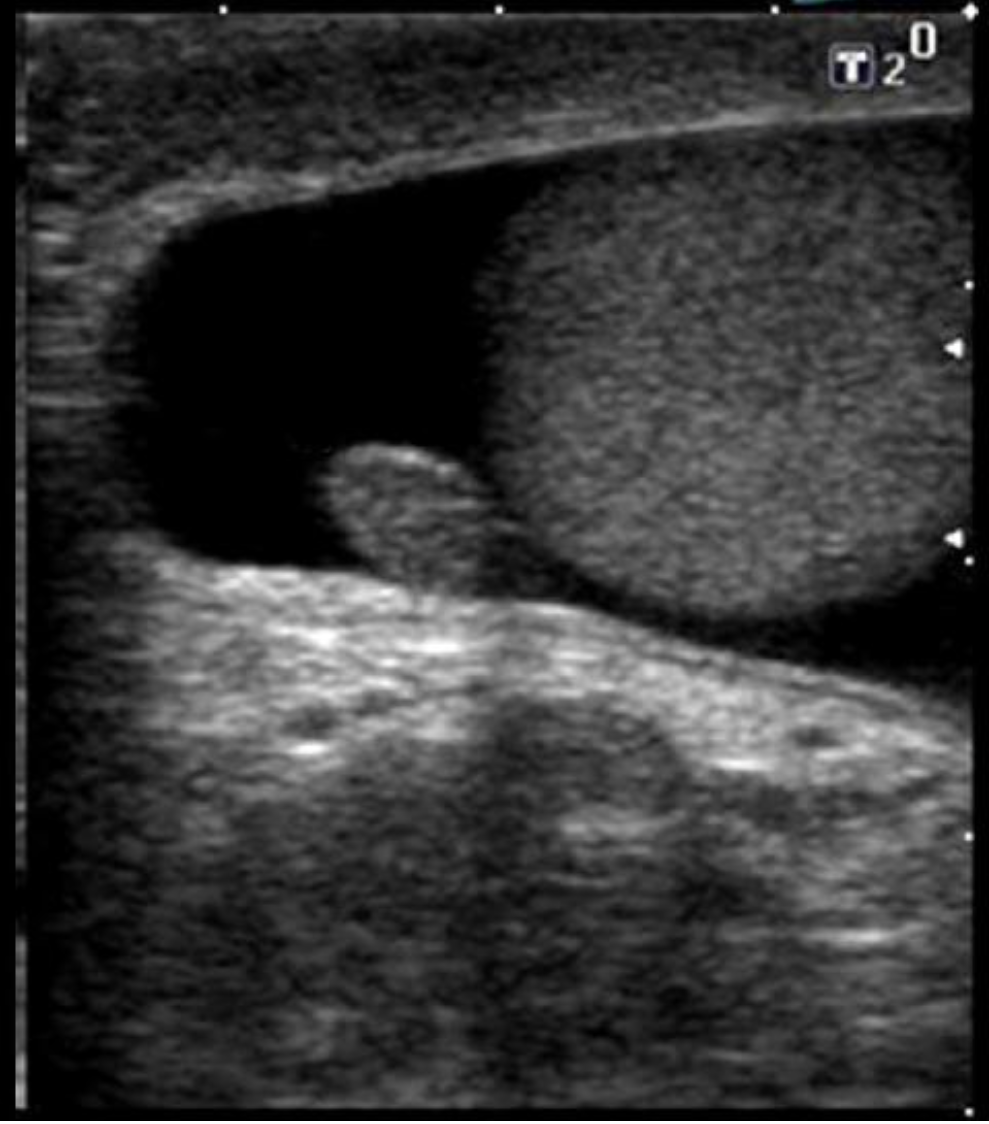

Which of the following correctly describes the findings on the image?

A. There is loculated hydrocele present.

B. There is an extratesticular mass present.

C. There is an appendix teste present

D. There is a scrotal pearl present.

The appendix teste is a small ovoid structure usually located between the superior pole of the testicle and epididymal head. It is normally the same echogenicity of the epididymis.